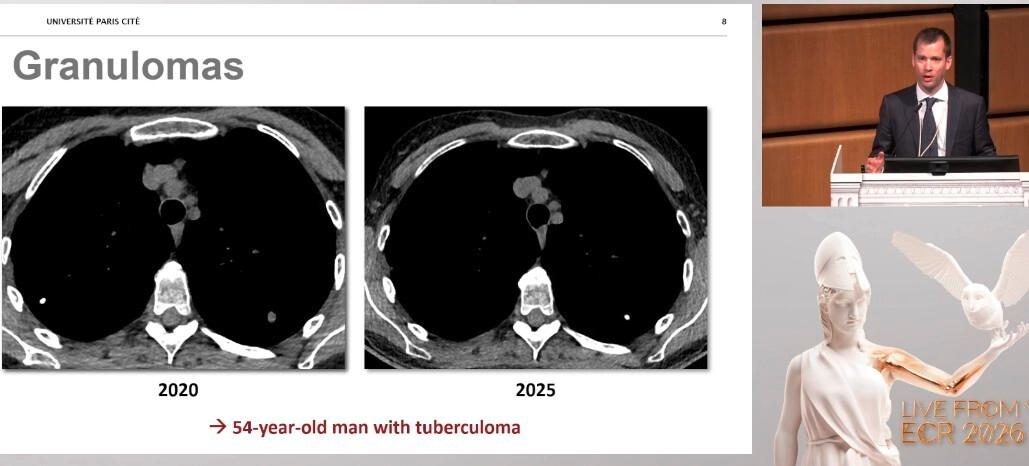

De fait, la grande majorité des nodules pulmonaires observés au scanner sont bénins, rappelle-t-il. En image